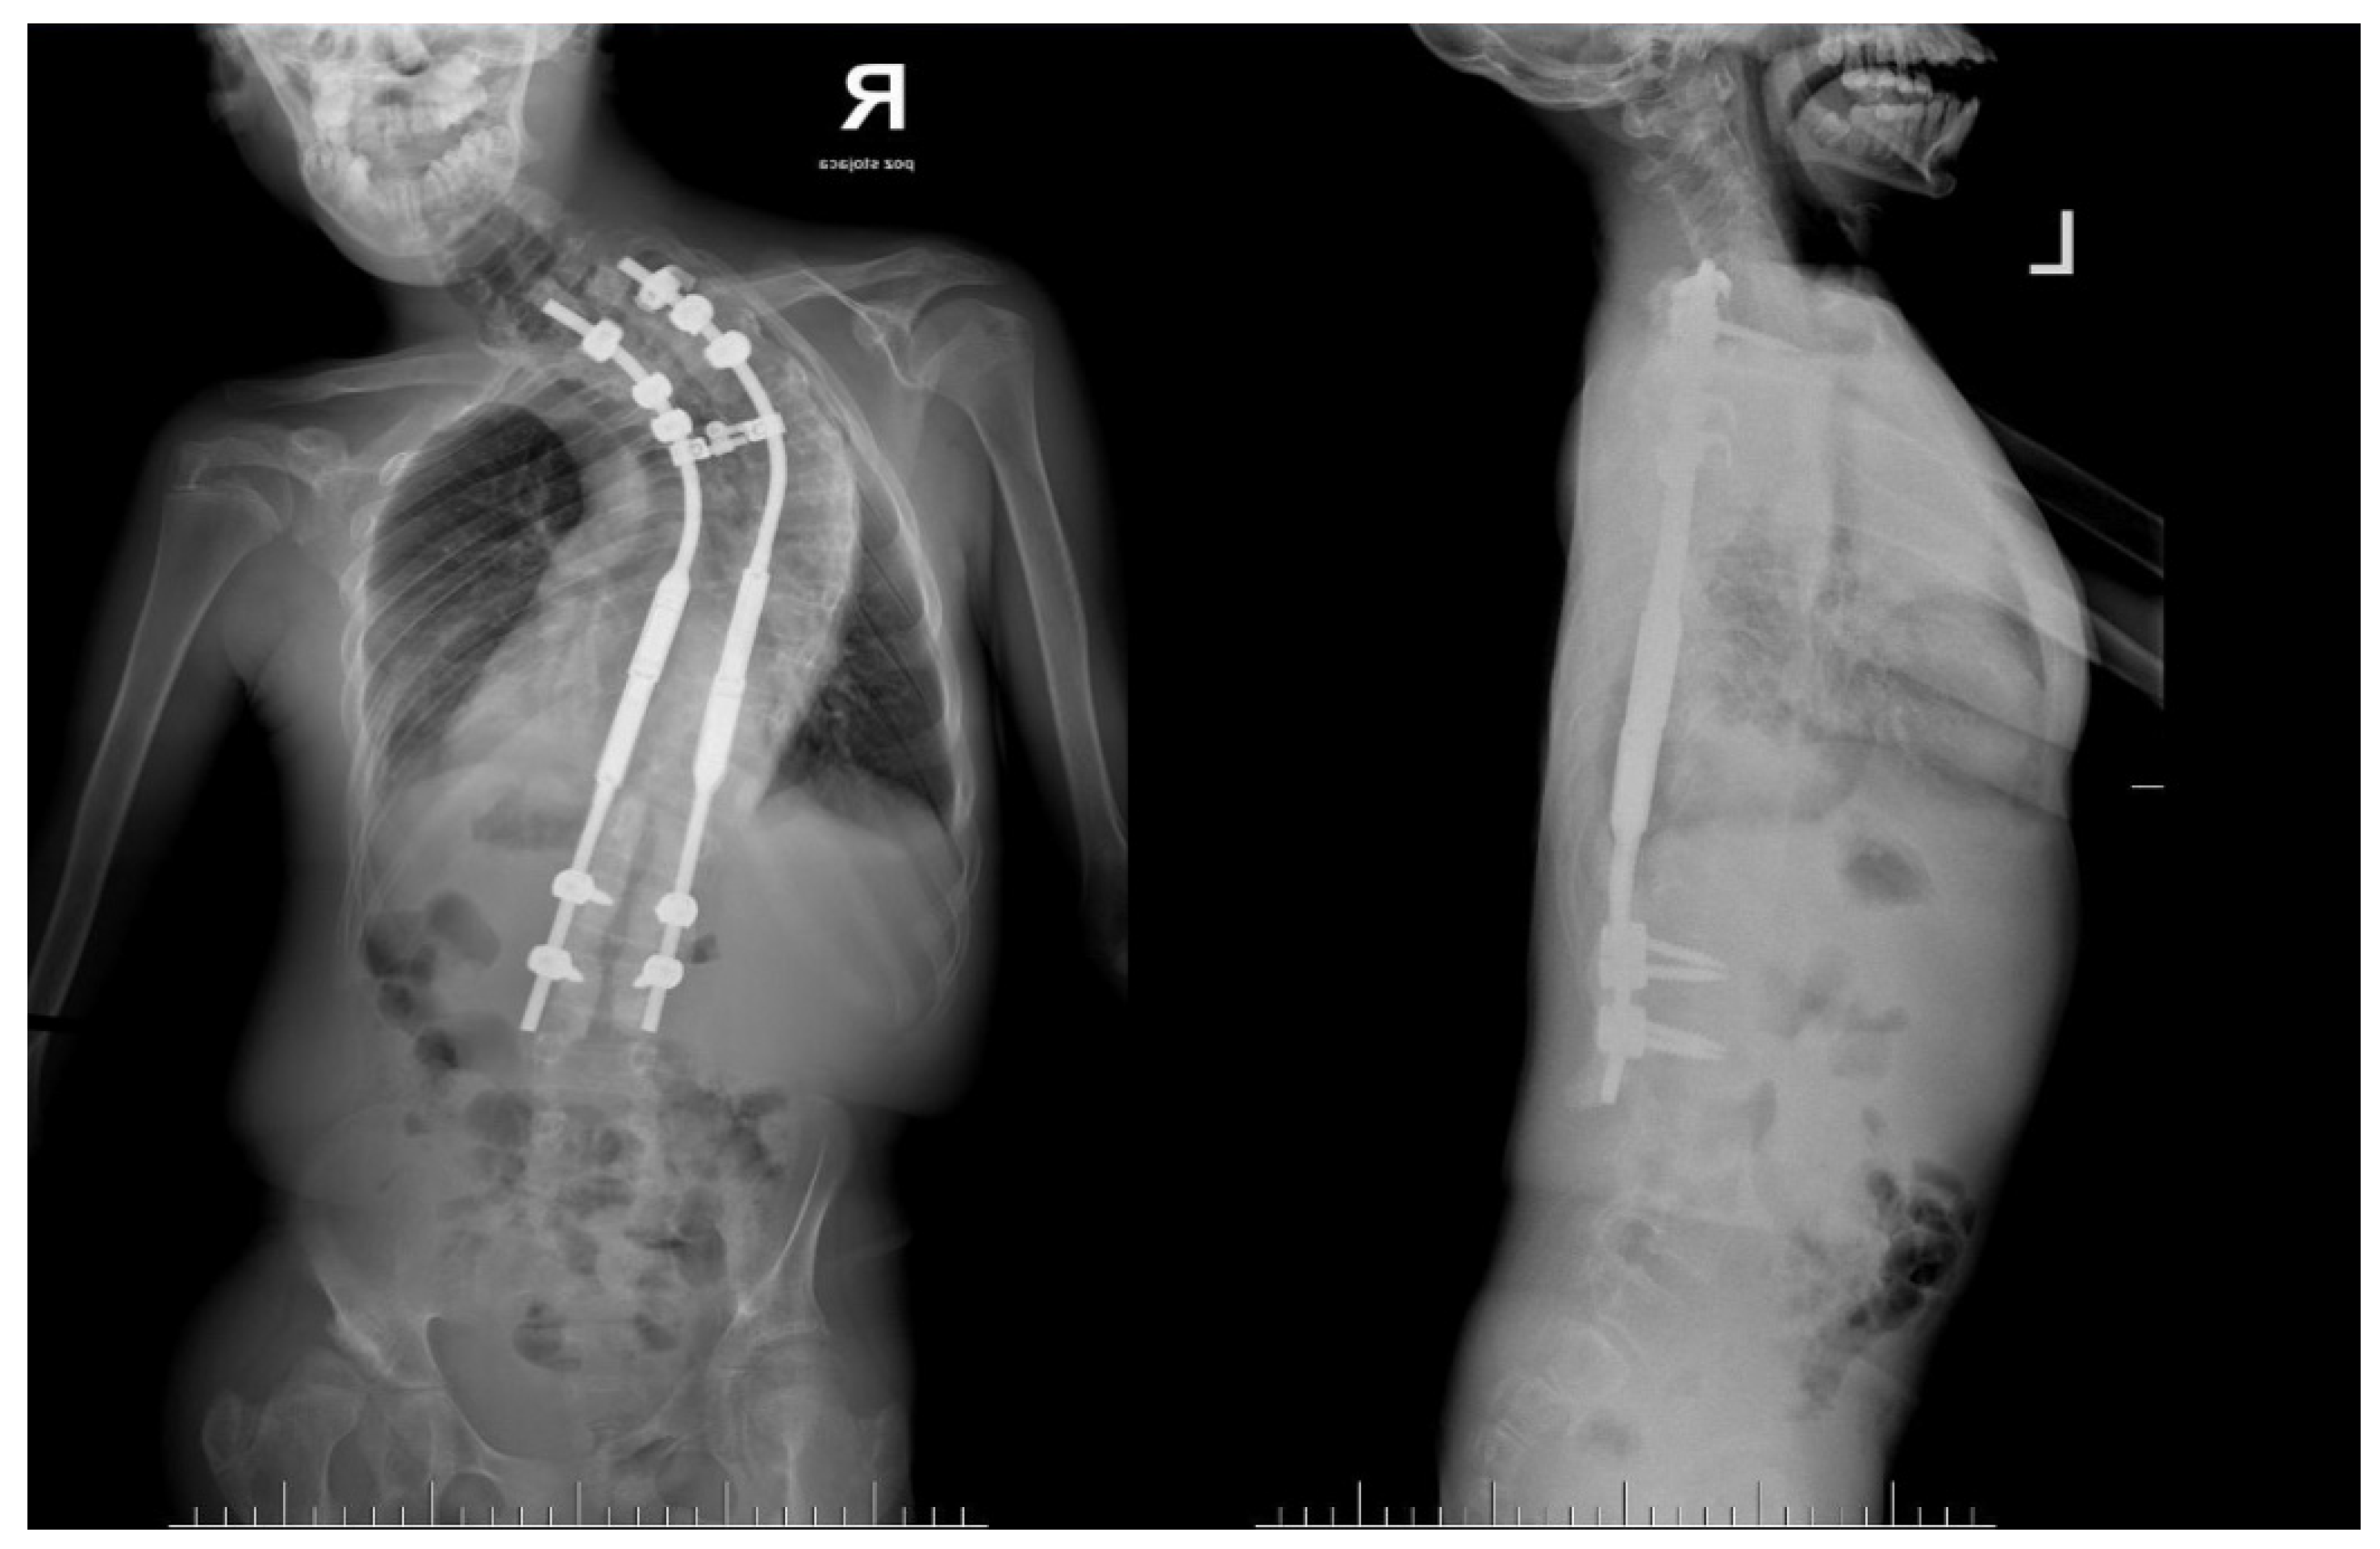

2. Case Presentation